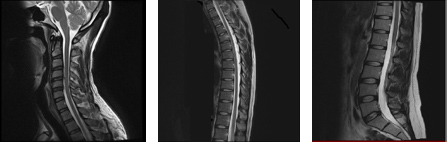

○脊椎